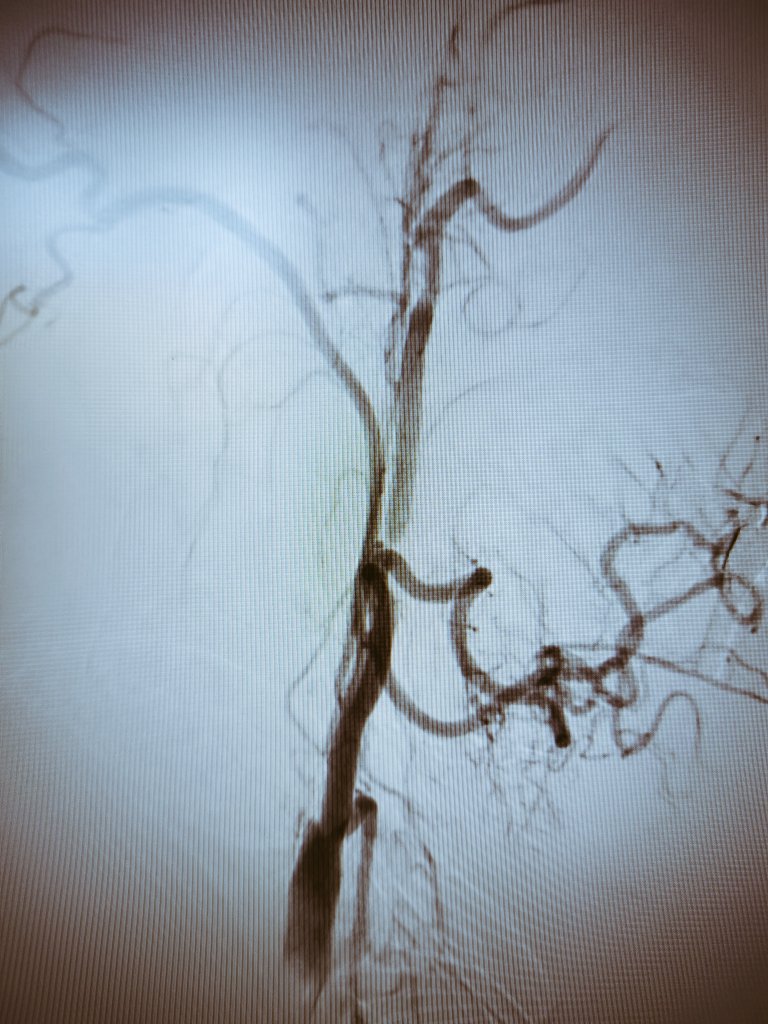

Thrombous at the tip of the iNstroke catheter @CARDIVAGROUP @iVascularGlobal and ICA stenting.

Stroke due to left tandem occlusion After crossing the ICA occlusion direct aspiration using nobel 4F iNstroke catheter @iVascularGlobal @CARDIVAGROUP was performed wirh complete recanalization Finally ICA stenting was performed with Wallstent @bostonmedical NIHSS 1 at discharge